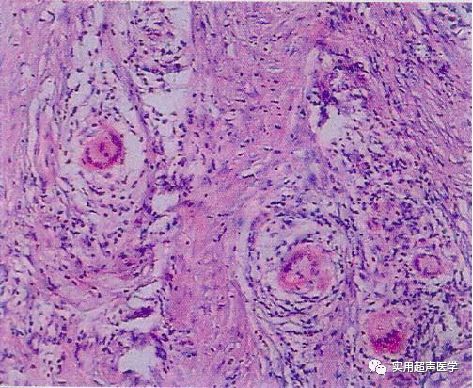

术中可见散在多发病灶

术后病理诊断:肉芽肿性小叶性乳腺炎

肉芽肿性乳腺炎是一类以肉芽肿为主要病理特征乳腺慢性炎症,包括多个临床病种,其中一种较为为多见,病因不明,肉芽肿性炎症以乳腺小叶为中心,故叫肉芽肿性小叶性乳腺炎(GLM),1972年Kessler首先报道,病名得到多数学者的认可。以前有人叫特发性肉芽肿性乳腺炎,乳腺肉芽肿或肉芽肿性小叶炎,是指乳腺的非干酪样坏死局限于小叶的肉芽肿病变,查不到病原体,可能是自身免疫性疾病,象肉芽肿性甲状腺炎、肉芽肿性睾丸炎一样,易与结核性乳腺炎混淆,以前发病率不高,所以,临床和病理医生都对其观察研究不多。